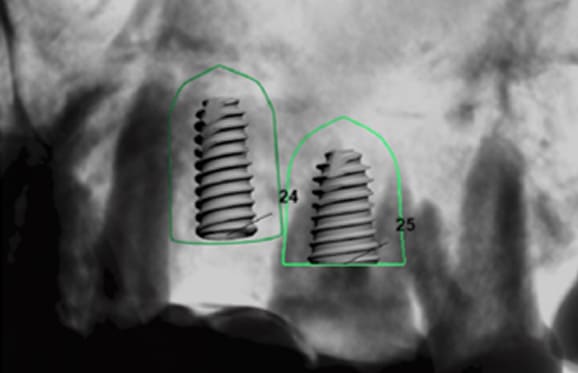

● 上の顎の奥歯にインプラントを入れるのに骨が足りないため、ソケットリフトと人工骨補填して骨造成を行った症例1

術前

藤沢デンタルオフィスのインプラント術前 藤沢デンタルオフィスのインプラント術前

3Dシミュレーション

術後

藤沢デンタルオフィスのインプラント術後 藤沢デンタルオフィスのインプラント術後

シミュレーション通りの上顎洞底挙上と人工骨補填(3Dガイドシステム使用)

● 上の顎の奥歯にインプラントを入れるのに骨が足りないため、ソケットリフトと人工骨補填して骨造成を行った症例2